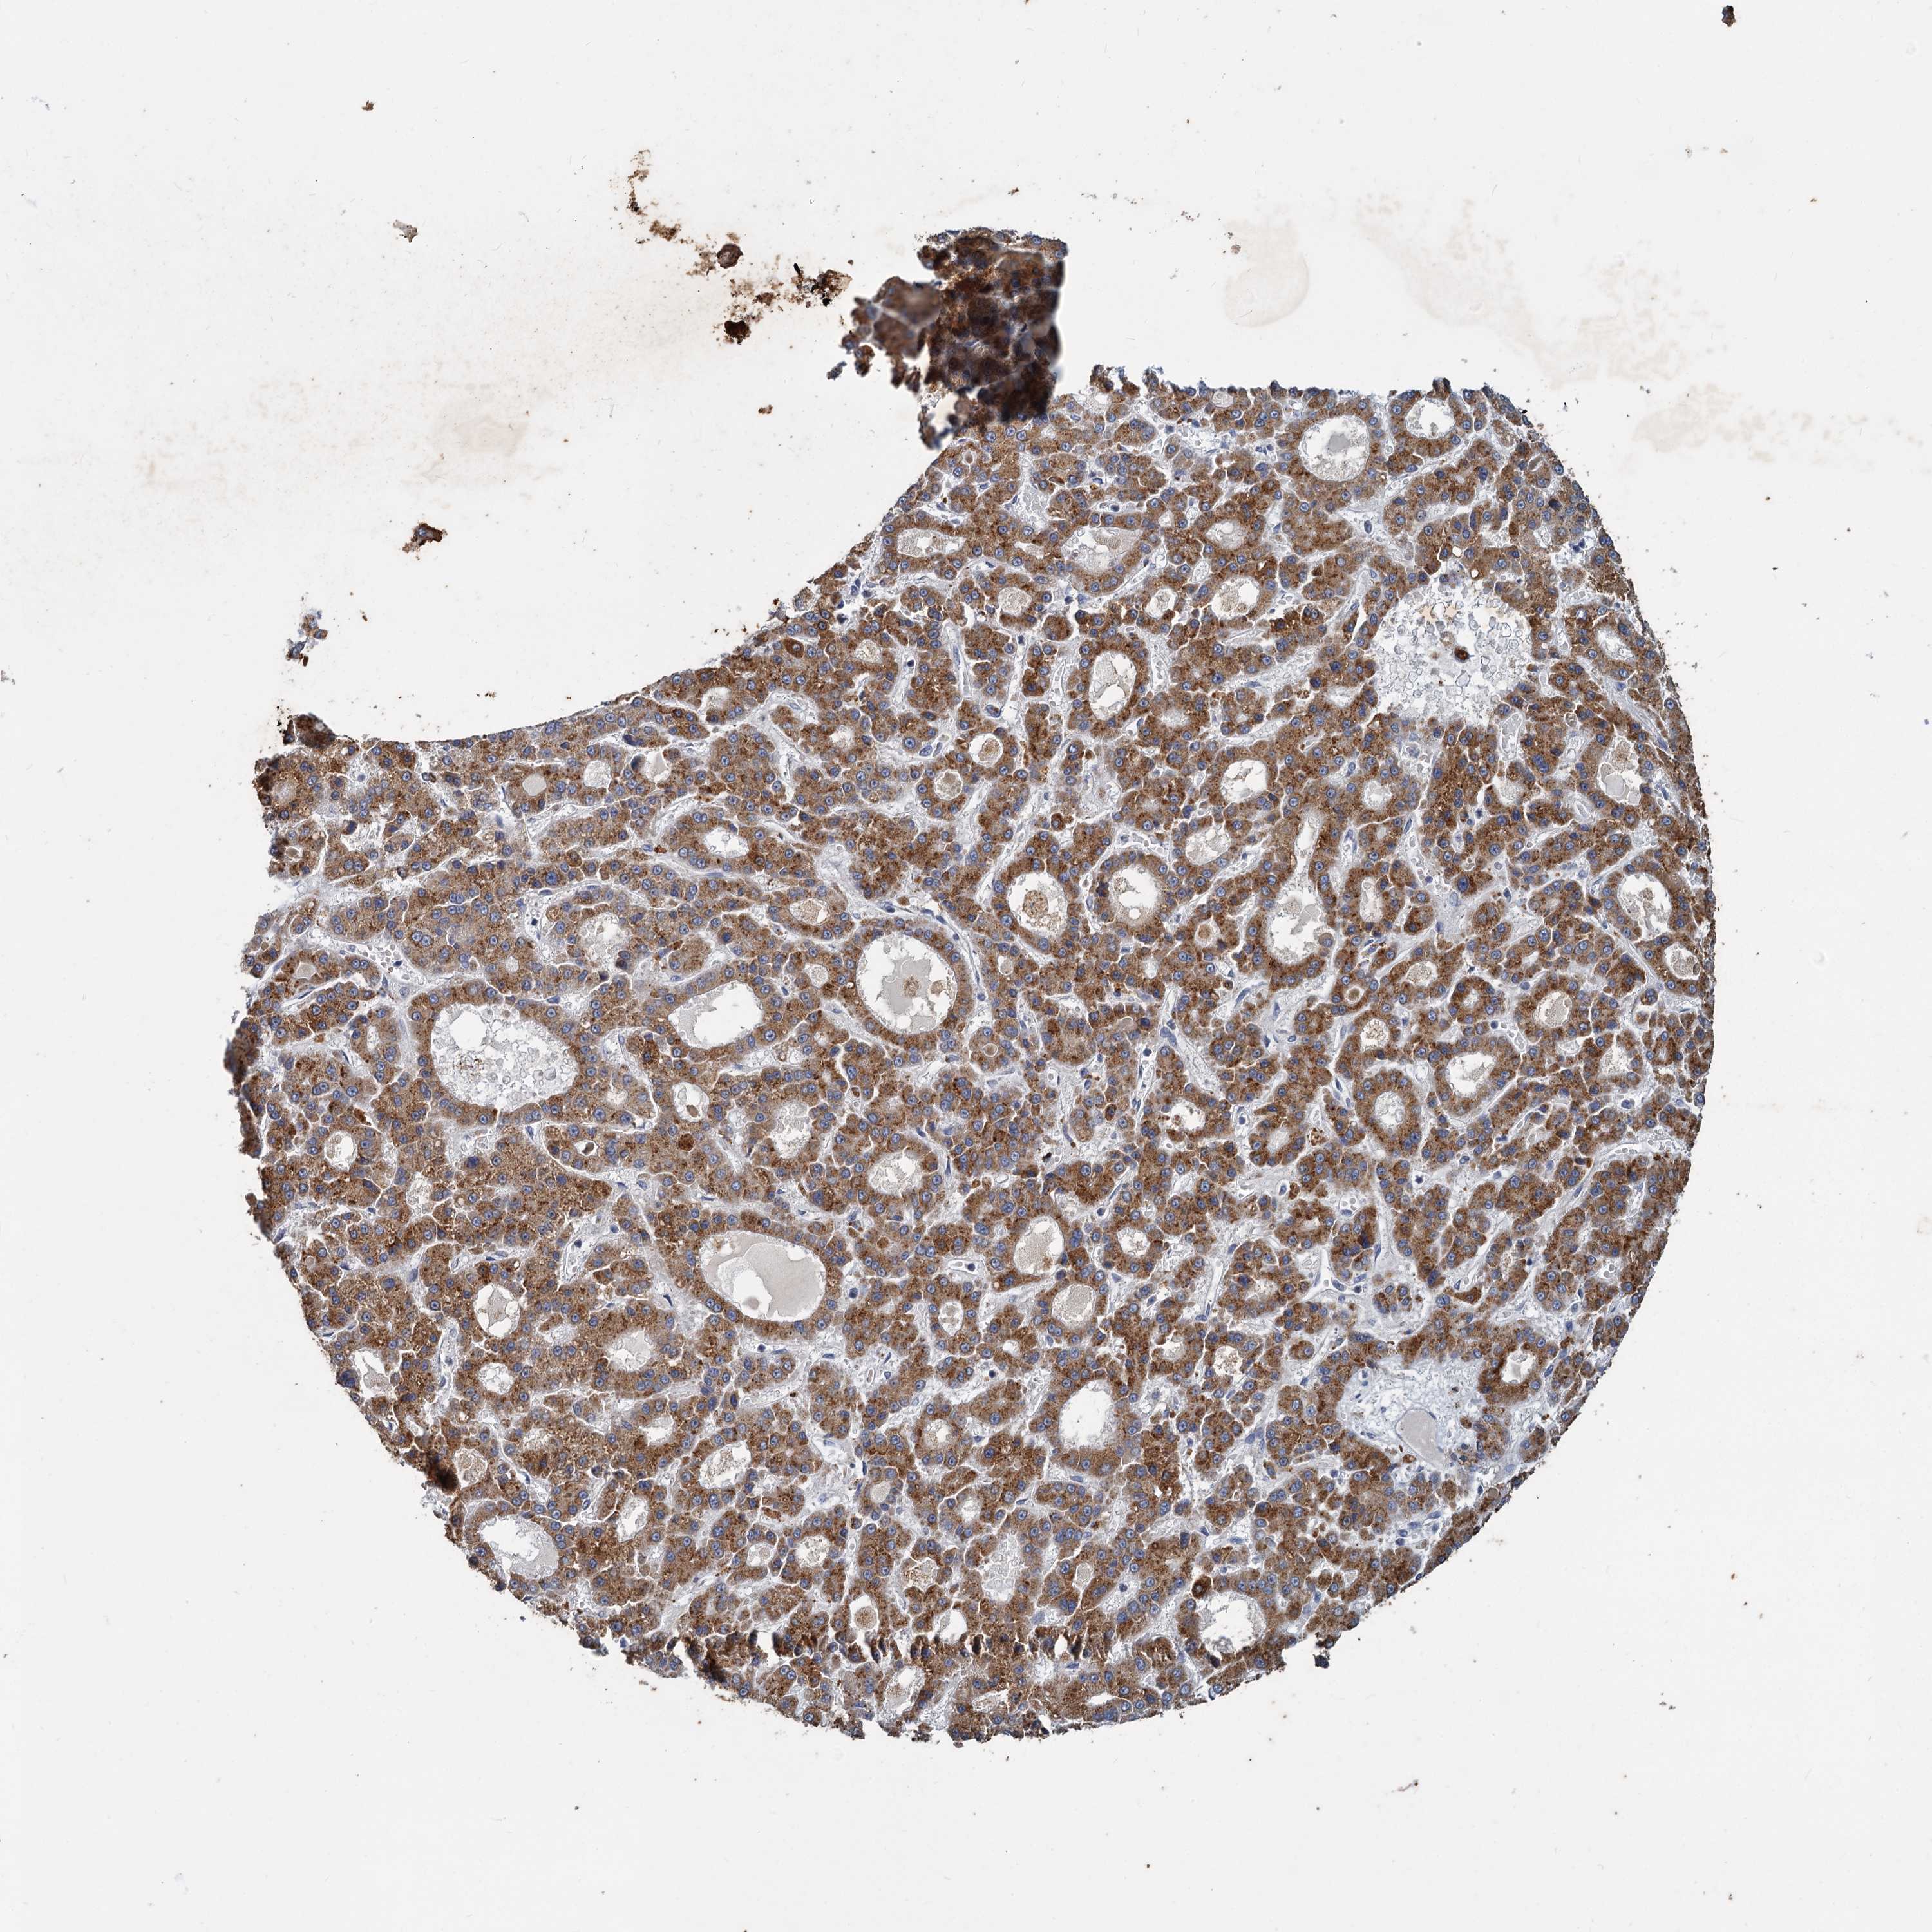

LIVER CANCER - Protein expressioni

A mouse-over function shows sample information and annotation data. Click on an image to view it in a full screen mode. Samples can be filtered based on level of antibody staining by selecting one or several of the following categories: high, medium, low and not detected. The assay and annotation is described here.

Note that samples used for immunohistochemistry by the Human Protein Atlas do not correspond to samples in the TCGA dataset.

Antibody stainingi

Antibody staining in the annotated cell types in the current human tissue is reported as not detected, low, medium, or high, based on conventional immunohistochemistry profiling in selected tissues. This score is based on the combination of the staining intensity and fraction of stained cells.

Each image is clickable and will lead to virtual microscopy that enables deeper exploration of all samples and also displays staining intensity scores, fraction scores and subcellular localization as well as patient and tissue information for each sample.

Antibody HPA039931

Staining

High

Medium

Low

Not detected

Intensity

Strong

Moderate

Weak

Negative

Quantity

>75%

75%-25%

<25%

None

Location

Nuclear

Cytoplasmic/membranous

Cytoplasmic/membranous,nuclear

Cholangiocarcinoma

Carcinoma, Hepatocellular, NOS